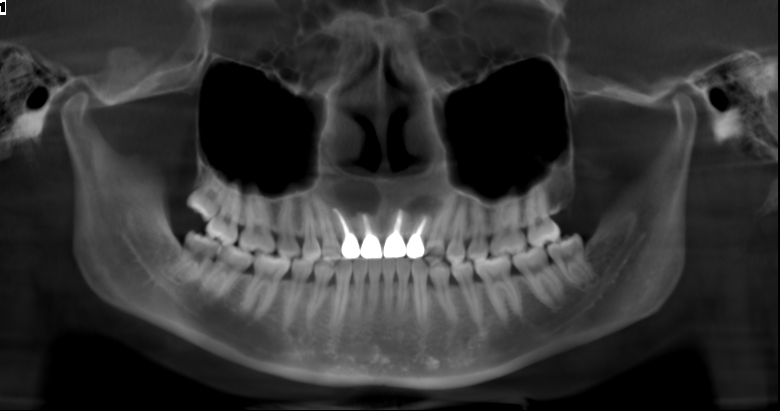

门诊X线片显示上颌骨存在低密度阴影,医生初步判断可能是囊肿复发。经过复查CBCT后,发现囊肿确实有所增大。“您看这里,这几个牙根周围出现了明显的阴影区,而且这个区域的骨壁已经变薄不连续了,这就是导致您鼻腔异味和肿胀感的根源。”医生指着三维影像向王先生解释道。检查发现,王先生口内前牙区有多个牙齿经过根管治疗和冠修复,其中一颗牙齿对应的唇侧黏膜可见小瘘管——这正是炎症向口腔内形成的“排脓通道”。